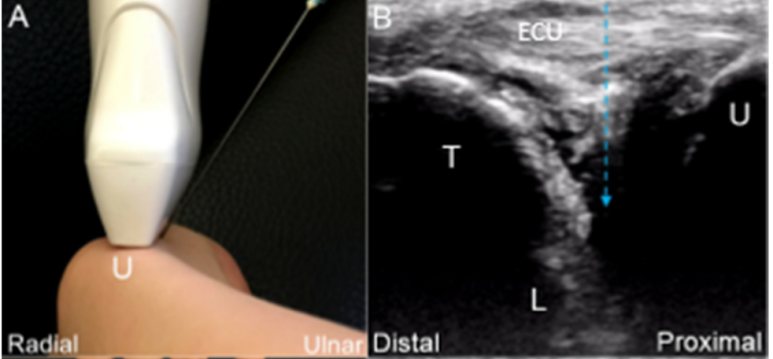

민트색 박스 표시한

척골 경상돌기(Sp)에 프로브를 대고

TFCC 장축 스캔을 하면요.

가장 바깥에

척측수근신근 힘줄이 보이고요.**

(ECU, extensor carpi ulnaris)

@ DOI: 10.3390/jcm8101540

그 아래에 파란색으로 표시한

척골 측부인대(Ulnar collateral ligament)

가 보입니다.

그 아래는 빨간색으로 표시한

반월 연골 유사체(Meniscus homologue)

가 보이고요.

그 아래는 귤색으로 표시한

요척 인대(Radio-Ulnar ligament)

얕은층(superior limb)와

깊은층(deep limb)으로 보입니다.

반월 연골 유사체 아래에는

보라색으로 표시한

월상 삼각 인대(Luno-Triquertral ligament)

그 아래에는 녹색으로 표시한

가장 중요한 구조물이죠.

바로 '삼각섬유연골' 이라는(Triangular fibrocartilage, TFC)

관절 디스크(Articular disc)가

요골에 붙어있습니다.